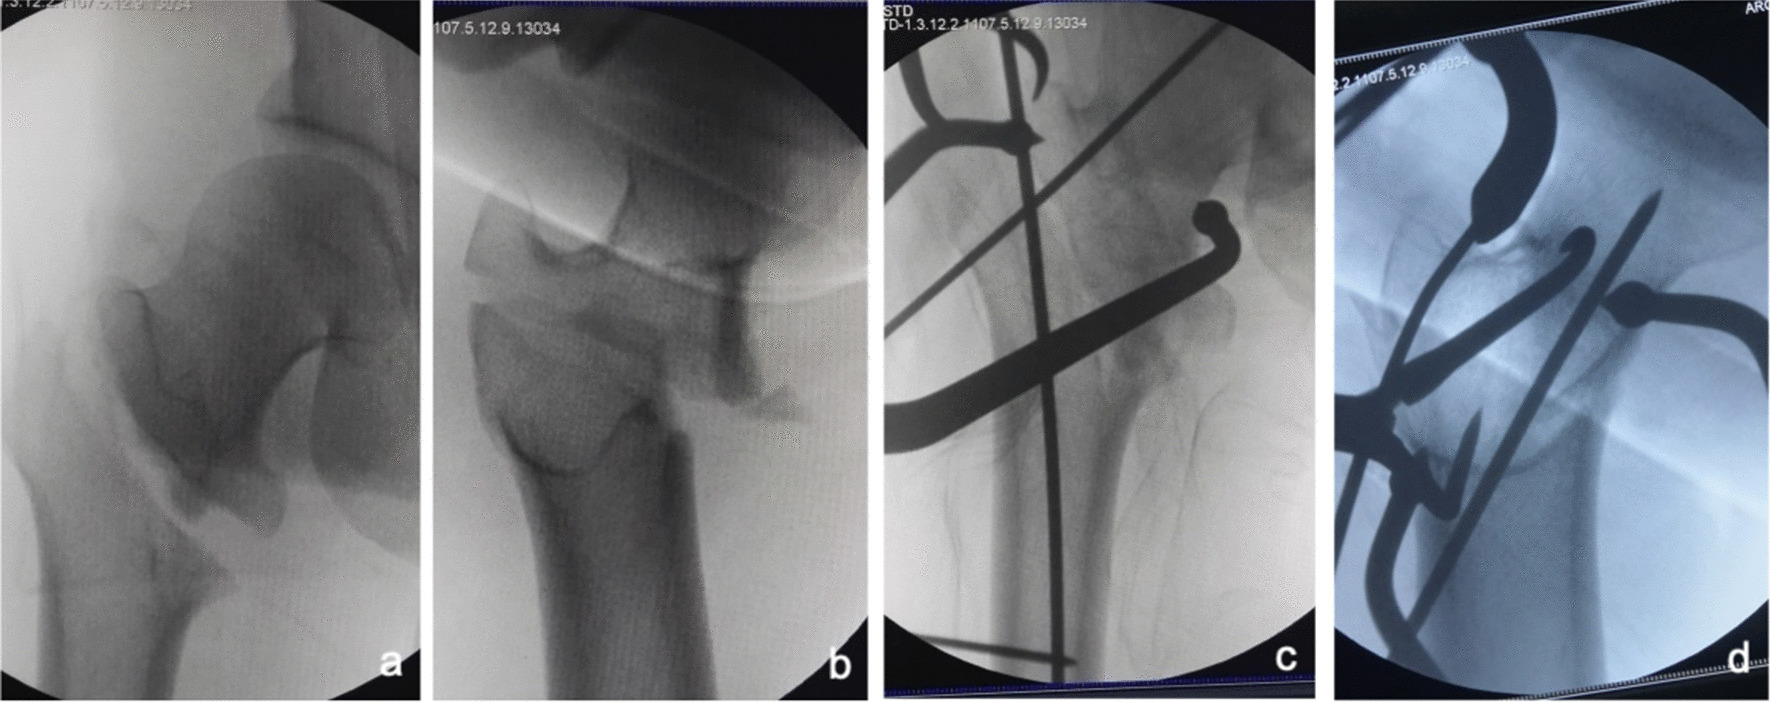

Fig. 7.

Anteroposterior and lateral X-ray films before and after reduction in patients with difficulty in reduction on both sagittal and coronal planes and pronation and medial rotation displacement of the proximal fracture segment a, b Before reduction; c, d After reduction (one head placed in front of the proximal fracture segment and the other head behind the greater trochanter)